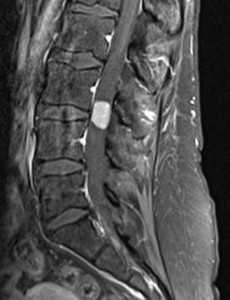

Миксопапиллярная эпендимома. Сагиттальная Т1-зависимаяМРТ после контрастирования.